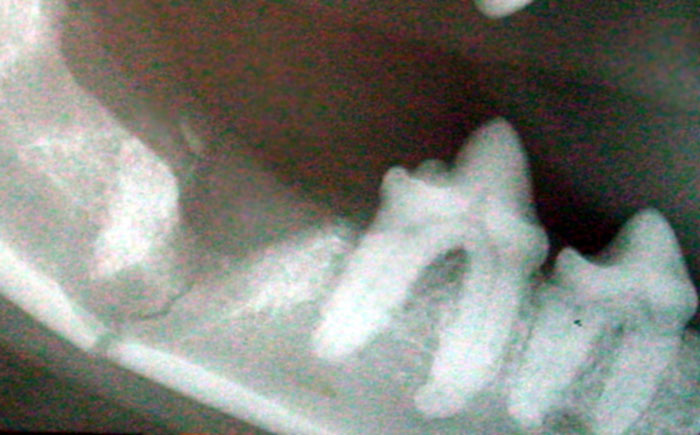

Fracture of mandible caused by excessive force extraction the lower carnassial tooth (molar 1)

Diagram courtesy of Dr Robert Wiggs, Dallas Dental Service for Animals, Dallas, Texas, USA